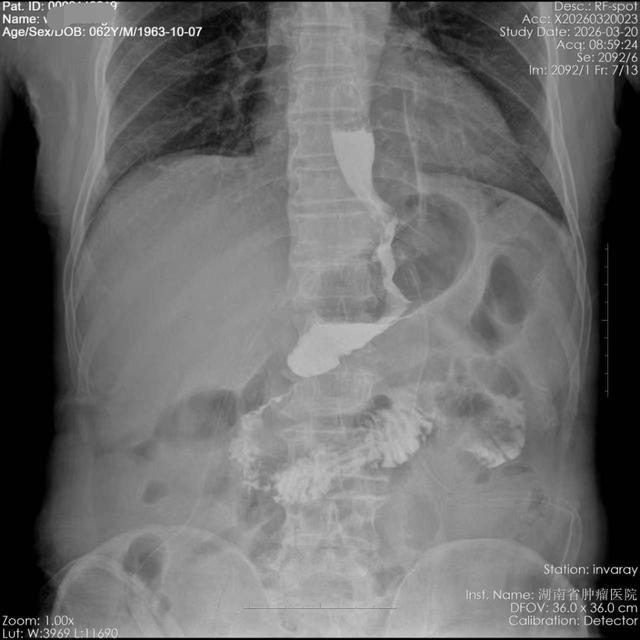

手术历时4小时顺利完成。术后造影检查显示,患者吻合口通畅,即便在头低脚高位亦未见反流现象。患者于术后第7天康复出院。

(▲站立位:吻合口通畅)